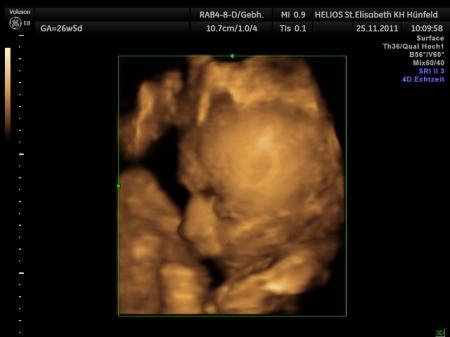

Hallo Ihr Lieben, heute hatte ich nun wieder Termin zum CTG und zum 3.Screening! Meinem Kleinem geht es super! Beim CTG waren null Wehen zu sehen und auch der US war super! Fruchtwassermenge ist auch okey wieder! Letztes Mal war diese ja etwas hoch! Hat sich also jetzt wieder normalisiert! Ich habe mit meinem Arzt auch kurz über den KS gesprochen und ich bekomme dann Anfang des Jahres eine Überweisung für das Planungsgespräch! Morgen komme ich in die 32.SSW und mein Kleiner ist jetzt ca. 42cm und 1700Gramm schwer! Hier nochmal die genauen Daten: BDP: 8,2 FOD/KU: 10.2 ATD: 7,9 APD/AU: 8,0 FL/HL: 6,0 Blutdruck war okey mit 115/70, Urin auch einwandfrei..kein Eweiß o.ä.! Mein Kleiner liegt in SL, Fundus ist bei RS-3 und zugenommen habe ich nun insgesamt 8Kilo! Also alles super und ich freue mich riesig Achja ich soll jetzt wöchentlich zum CTG kommen wegen meiner Vorgeschichte! Schönen Abend Euch noch und LG Anja